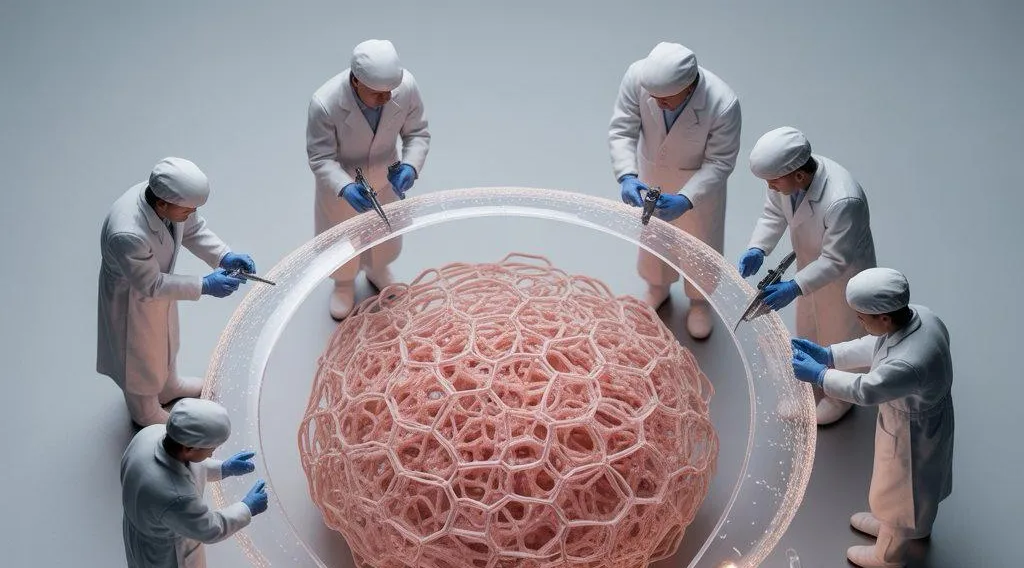

▪️ Получаем максимум из плазмы пациента для запуска регенеративной функции с помощью факторов роста.

▪️ PRGF в трихологии: обоснование и клиническая эффективность.

▪️ Что представляет из себя регенеративная лаборатория Ycellbio?

▪️ Уникальные особенности технологии и легкость применения умной пробирки YCELLBIO.